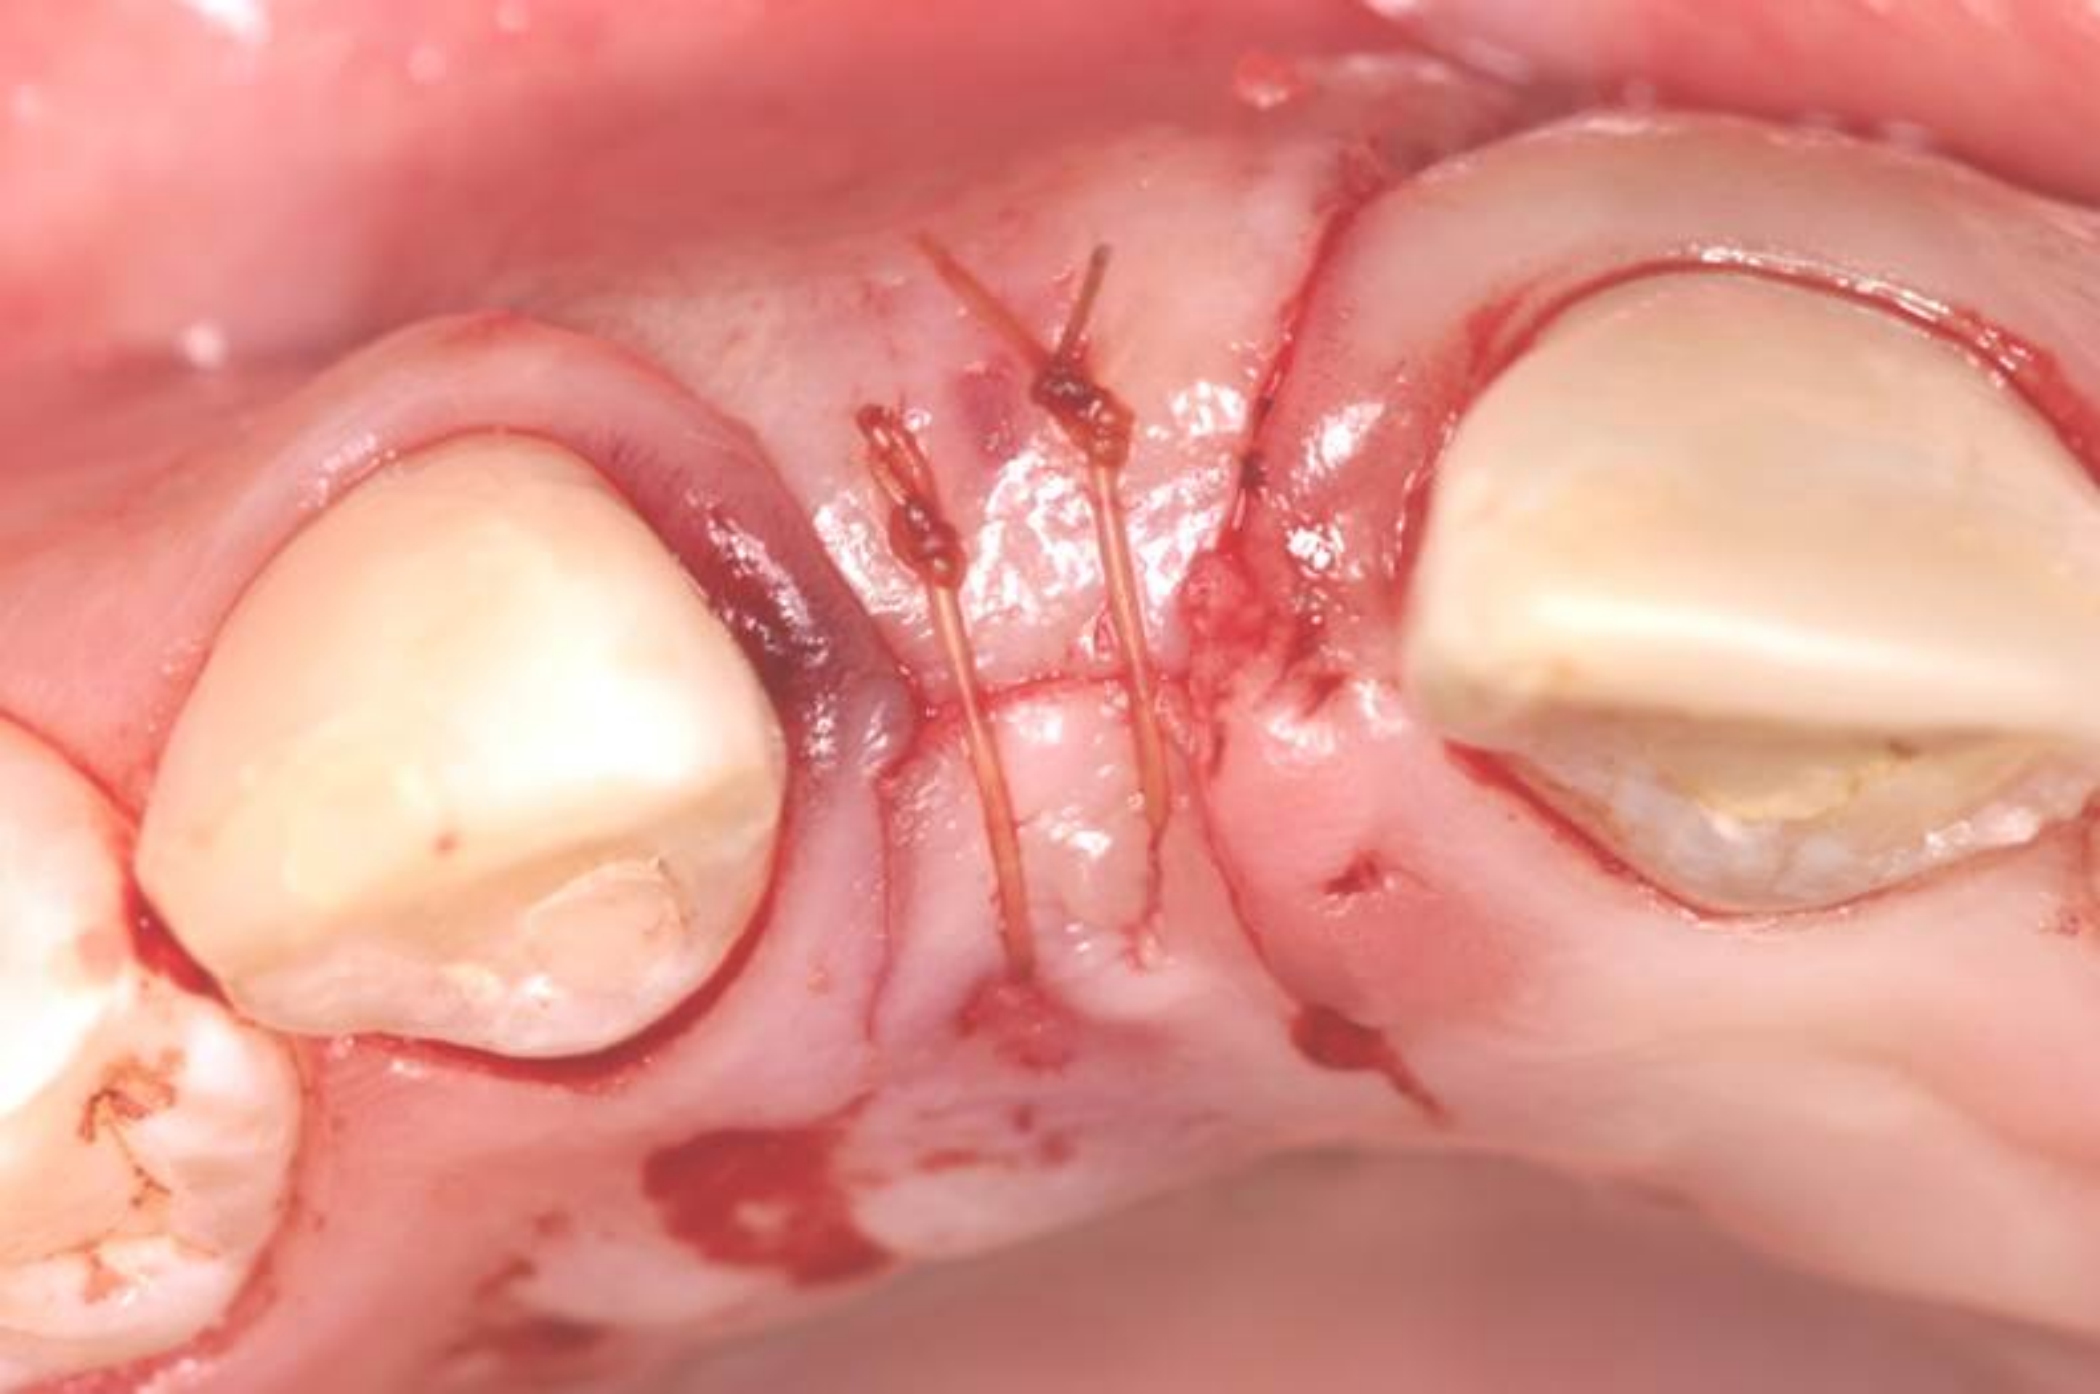

Fig 7. Vertical releasing incisions sutured to attain primary closure, buccal view.

Figure 7

Fig 8. Submerged implant protocol, occlusal view. A horizontal releasing incision was sutured to attain primary closure. Note that there are no sutures through the thin retained papillary segments.

Figure 8